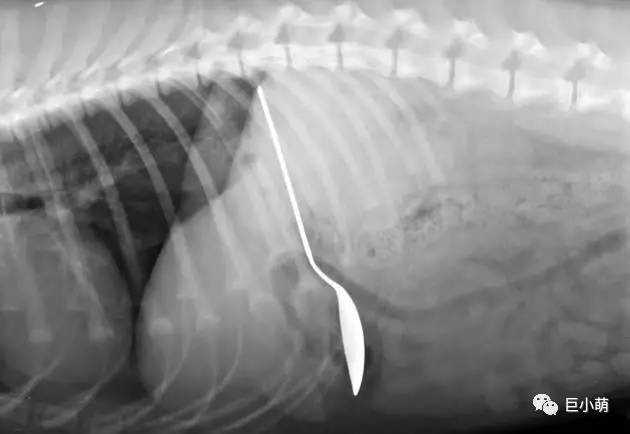

看过一档美国的宠物医疗节目,一个主人喜欢用勺子直接喂花生酱给狗狗吃,结果狗狗一高兴连铁勺子一并吞进去了……

异物堵住胃肠道,尖锐的物品(别针、缝衣针、小型玩具、超硬的骨头等)扎伤胃肠道;